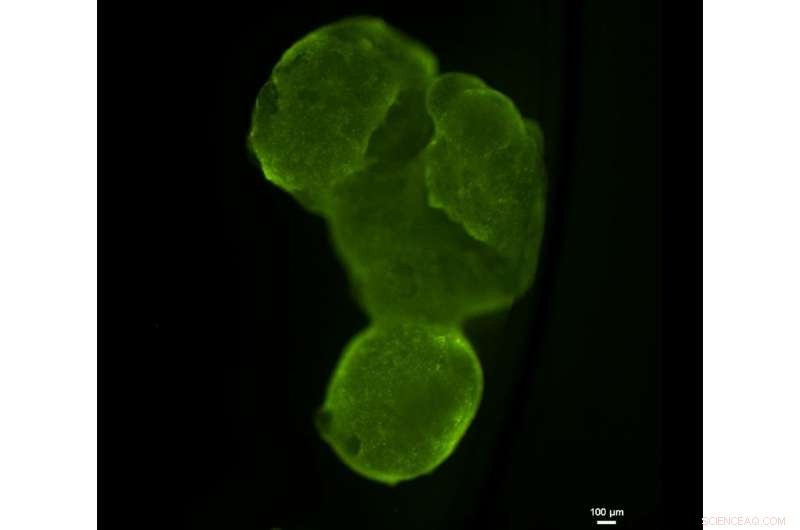

In a new study, Tel Aviv University researchers reveal how they invented the first fully personalized tissue implant, engineered from a patient's own materials and cells. The new technology makes it possible to engineer any kind of tissue implant from one small fatty tissue biopsy.

The researchers extracted a small biopsy of fatty tissue from patients, then separated its cellular and a-cellular materials. While the cells were reprogrammed to become induced pluripotent stem cells—able to make cells from all three basic body layers, so they can potentially produce any cell or tissue the body needs to repair itself—the extracellular material was processed to become a personalized hydrogel. After combining the resulting stem cells and the hydrogel, the scientists successfully engineered the personalized tissue samples and tested the patients' immune responses to them.